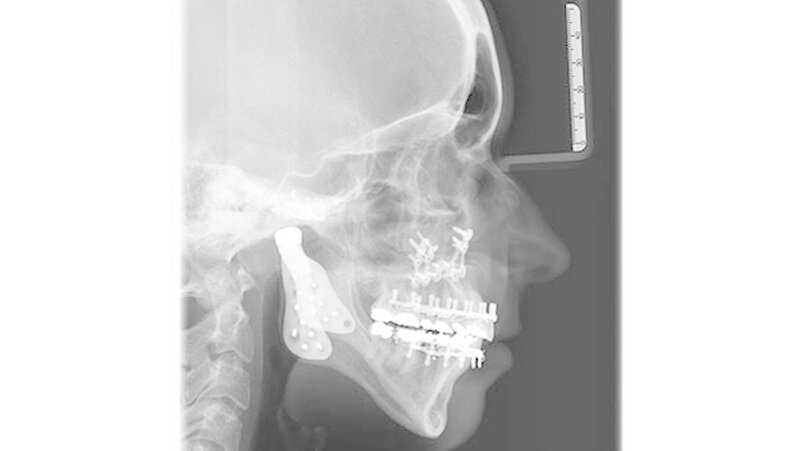

Das Bonner MKG-Chirurgenteam um Prof. Dr. Dr. Rudolf Reich diagnostizierte eine zunehmende Einschmelzung (Resorption) der Kiefergelenkfortsätze, wodurch die gesamte Abstützung des Unterkiefers am Schädel verloren gegangen war.

Da in diesen Fällen eine sichere Wiederherstellung der Abstützung des Unterkiefers mit eigenem Gewebe wie beispielsweise Knochen nicht möglich ist, weil eine erneute Einschmelzung droht, hat sich der Kiefergelenkersatz mit Endoprothesen bewährt.

Mit der virtuellen Planung, individuellen Kiefergelenkprothesen und einer zusätzlichen Rückpositionierung des Oberkiefers in die ursprüngliche Lage erfolgte dann die Operation. Alles erfolgte in einem Operationsgang. Die Bonner MKG-Chirurgen fertigten die Endoprothesen für die Frau individuell im CAD-/CAM-Verfahren an. Dafür wurden die Daten der Computertomografie des Schädels zugrunde gelegt.

Durch diese hoch anspruchsvollen Verfahren ließ sich annähernd die ursprüngliche Position des Unterkiefers vor der Einschmelzung wiederherstellen; in der gleichen Operation wurde die Position des Oberkiefers der jetzt idealen Stellung des Unterkiefers angepasst.